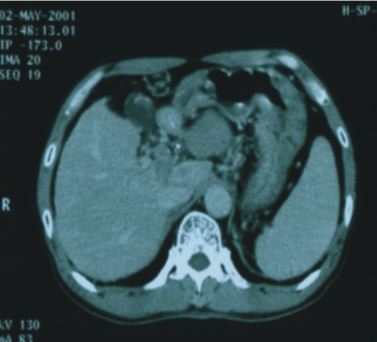

56歲/男性 (肝癌合併後腹腔淋巴腺轉移) |

74歲/男性 (直腸癌合併後腹腔淋巴腺轉移) |

||

| 90/5/2

(治療前) |

90/6/30(治療後) |

90/8/16(治療前) |

90/12/21(治療後) |